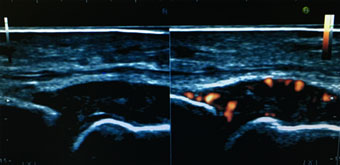

関節エコーの普及

RA診療においても、関節エコーはリウマチ性疾患に特徴的な炎症や骨破壊を鋭敏に捉えることができ(図8)、リウマチ診療においても診断や疾患活動性評価に有用とされています。AORAでは、関節エコー技術の普及を目的に、AORAメンバーのみならず、関連病院の検査技師の方々を対象として、勉強会を開催しエコー技術の普及を行なっております。関節エコーにより、より高度なRA診療を目指しています。

図8 RA患者さんの関節エコー画像